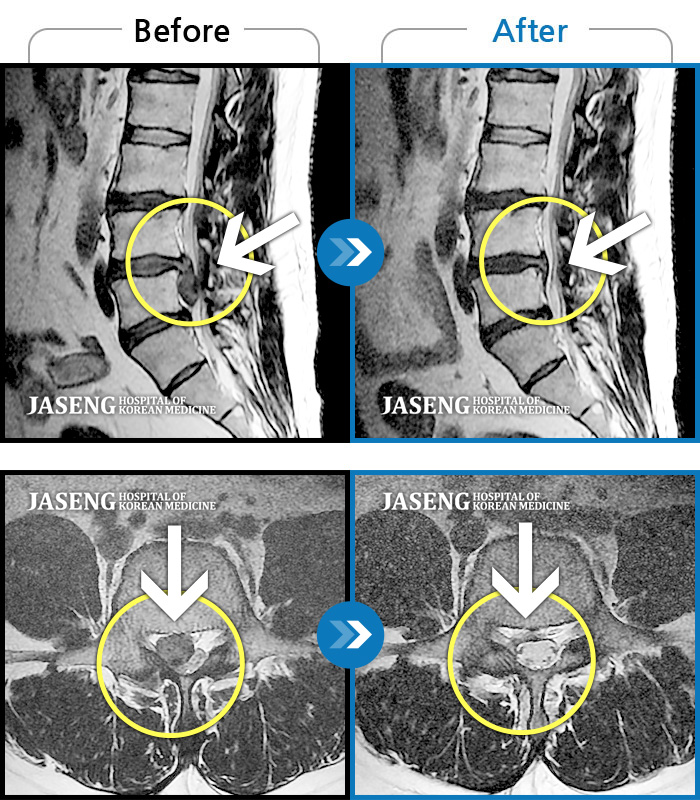

허리디스크

일산 · 김태용 원장

허리 골반통증이 극심했다.

촬영시기

2021.02.06 ~ 0222.01.15

2022.01.17